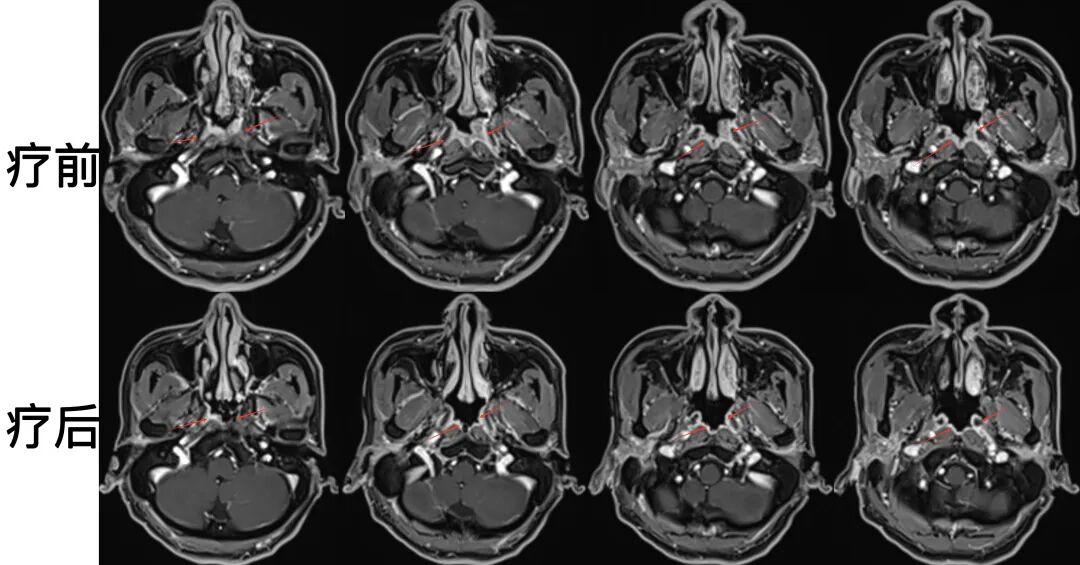

病例1:33歲女性患者,鼻塞、耳悶、涕中帶血為主要癥狀。磁共振檢查可見鼻咽區(qū)腫物侵犯雙側(cè)鼻咽腔,左側(cè)為著,侵犯翼突區(qū),屬于局部晚期鼻咽癌?;颊咧委熀?,病灶完全縮退,癥狀緩解,達(dá)到局部腫瘤的完全控制。

圖注:治療前后比對(duì)。上排為治療前,可見鼻咽病灶累及兩側(cè)腭帆張肌、提肌、左側(cè)翼內(nèi)肌及左側(cè)翼突內(nèi)外側(cè)板;下排為治療后,鼻咽區(qū)腫瘤病灶完全消失。治療過程中患者耐受性良好,未出現(xiàn)嚴(yán)重副反應(yīng)。